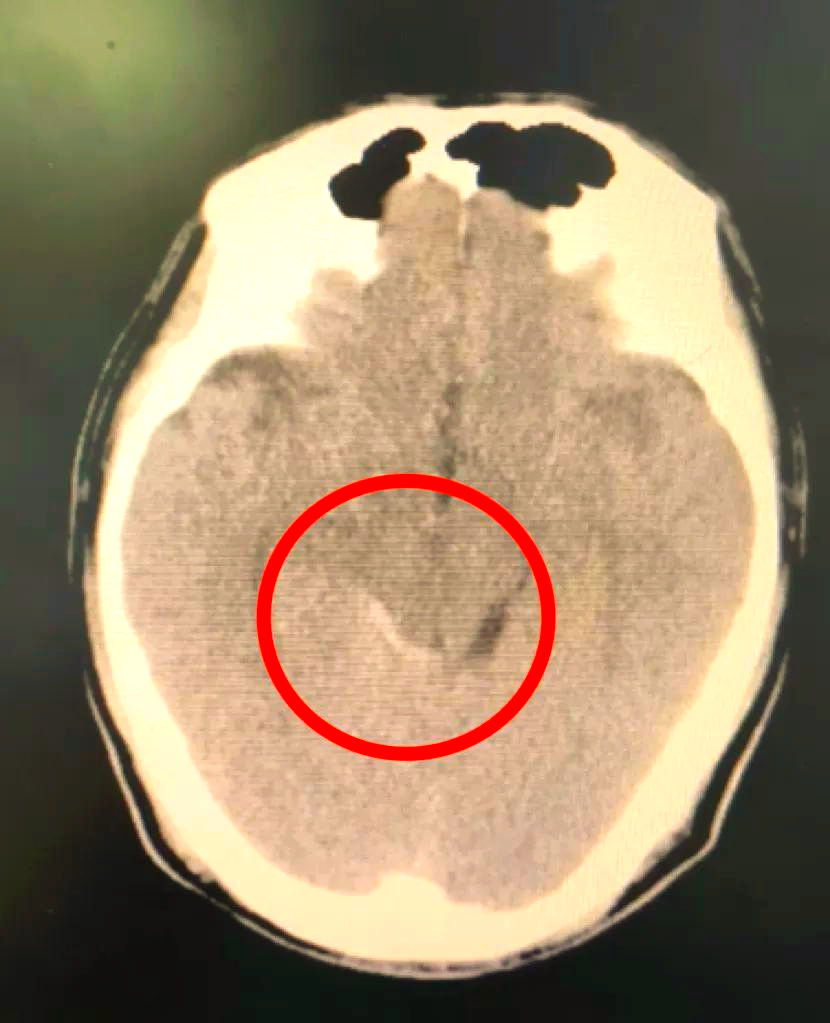

女.58岁 发现颅内动脉瘤2个月.

术前ct术后ct动脉瘤已夹闭